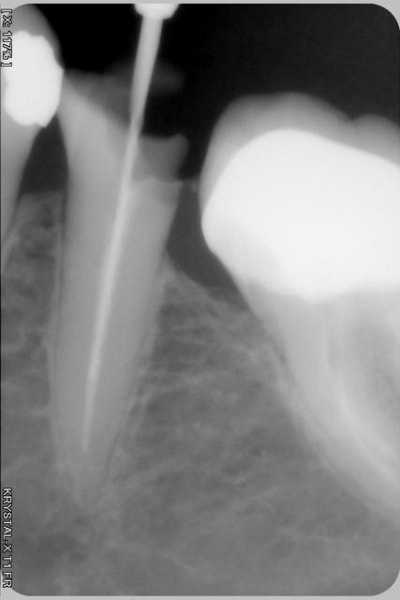

ici c'est un cliché ERML

qualité inférieure malgré le caractere récent du matériel ( mais usagé du capteur )

les trous de basse résolution sont très peu visibles